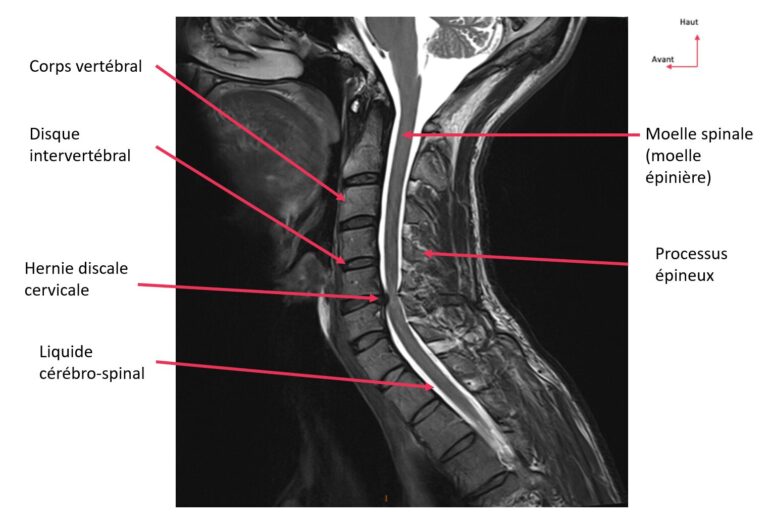

arthrodèse cervicale

Figure 1. Arthrodèse cervicale